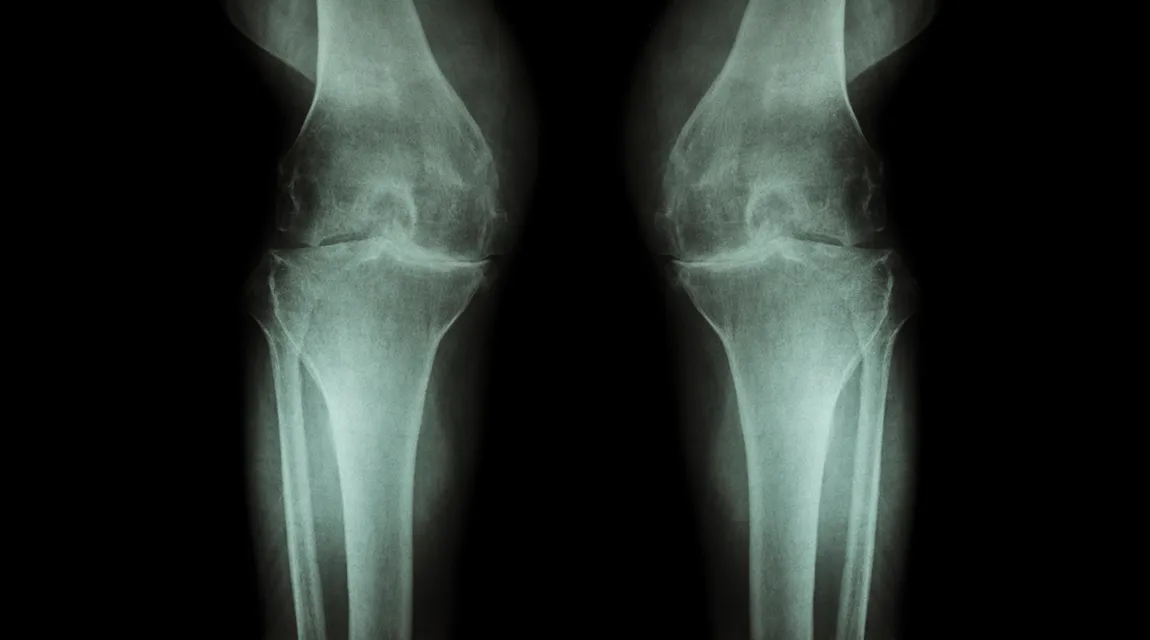

Die gewichtsbelasteten Knie- und Hüftgelenke sind dabei von der Arthrose besonders häufig betroffen. Mit dem langsamen, aber fortlaufenden Abbau von Gelenkknorpel beginnt die Krankheit. Unbehandelt führt Arthrose im Spätstadium zu einer beschädigten oder zerstörten Gelenkfläche, bei der Knochen auf Knochen reiben, was zu starken Schmerzen führen kann.